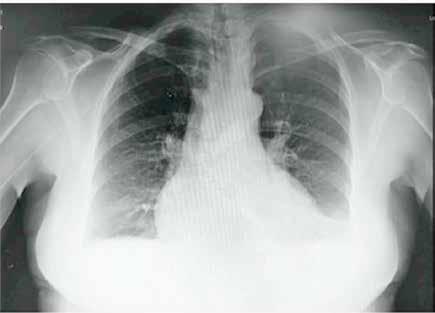

Se revisaron las pruebas solicitadas en Urgencias. En la analítica se en contró una hemoglobina (Hb) de 14 g/dl, un volumen corpuscular medio (VCM) elevado (106μ³) compatible con su historia de alcoholismo o con un déficit de ácido fólico o vitamina B12, una discreta elevación de la proteina C reactiva (13,2 mg/dl) sin elevación de otros reactantes de fase aguda y unas enzimas hepáticas dentro de la normalidad, con la aspartato transfe rasa ligeramente elevada 39 U/L (rango de normalidad: 5-34). Los tóxicos en orina fueron negativos, así como la etanolemia. La radiografía (rx) de tórax mostraba una condensación en el lóbulo superior izquierdo en posi ble relación con la infección tuberculosa diagnosticada en 2011 (Figura 1). La TC -a pesar de no mostrar signos de patología aguda intracraneal, ni masas ni signos de sangrado- sí que mostraba atrofia cerebral con surcos muy marcados, hallazgo no concordante con la edad de nuestro paciente (Imagen 2).

Figura 1. Radiografía de tórax en bipedestación AP y Lat.

Lesiones residuales/cicatriciales en campo superior izquierda, con aumento de densidad de parénquima, bronquictasias y pérdida de volumen, en relación con antecedente de TBC. Parénquima pulmonar derecho aceptablemente ventilado. Siluesta cardiovascular normal.